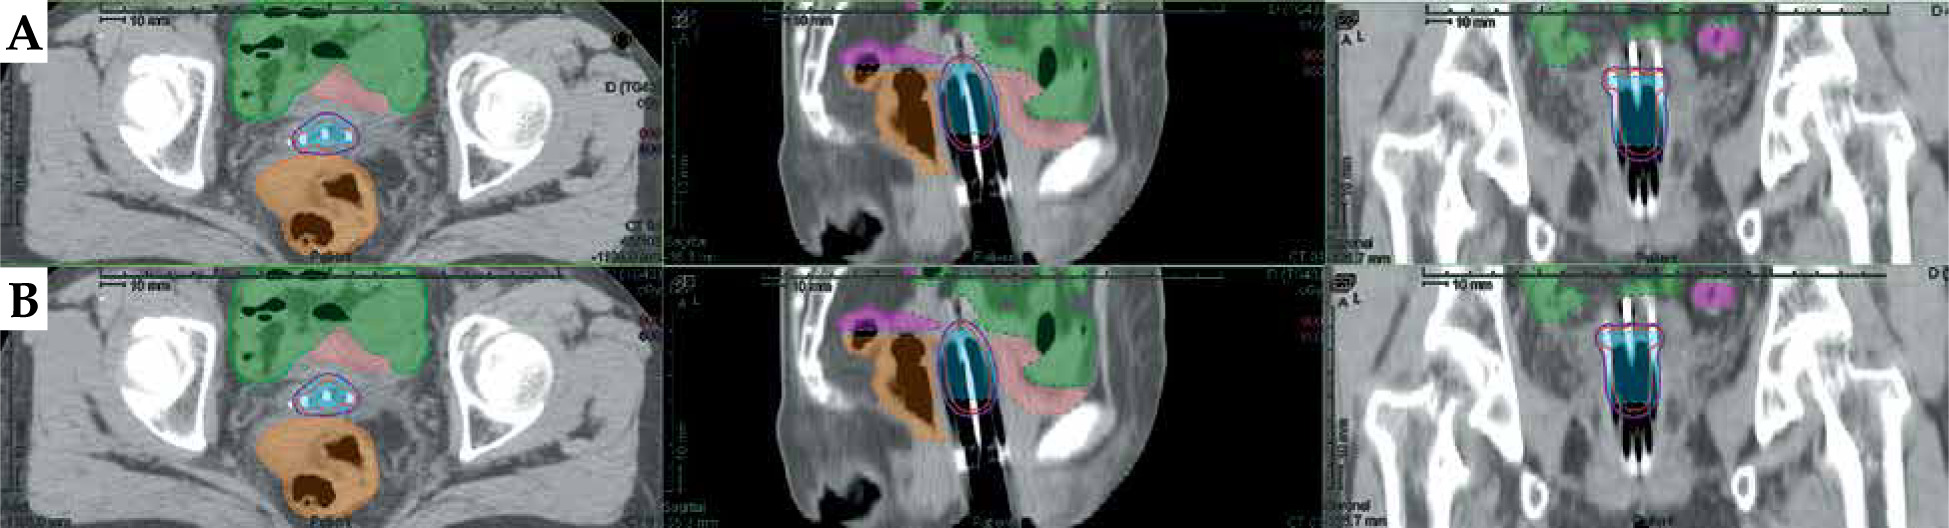

Fig. 5

Examples of dose distributions from manual and deep learning (DL)-based methods. A) Dosimetric results with manual reconstruction of the needles. B) Dosimetric results with automatic reconstruction of the needles. Purple lines represent dose distributions with 100% (600 cGy) prescription. Red lines represent dose distributions with 150% (900 cGy) prescription. Blue in the picture represents HR-CTV